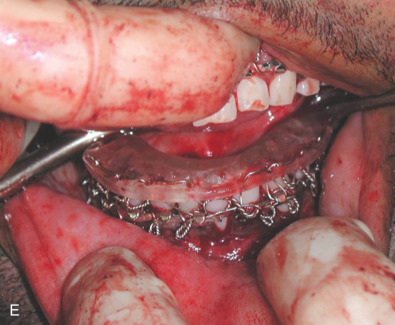

All of these systems allowed for convalescent function – life without MMF. RIF had the potential of dramatically shortening the course of treatment. However, its use was highly technique-sensitive with a steep learning curve. Thus, the incidence of complications increased dramatically due to operator error. Complications related to inadequate reduction – “the OIF” (open internal fixation … without the reduction) ( Figs. 1.16.1–1.16.3 ), inadequate fixation ( Figs. 1.16.4–1.16.7 ) and surgical misadventure ( Fig. 1.16.8 ) began to appear. Indeed, by the early 1990s operator error was the number one cause of mandibular fracture complications. Quite obviously, RIF is very unforgiving. When done poorly, one has a rigidly fixed mistake. The latest series of misadventures are related to the use of IMF screws. Bone-anchored arch bars will most likely be next. Not all believe that RIF and convalescent function is cost-effective with respect to the increased cost, potential for complications, and patient acceptance.